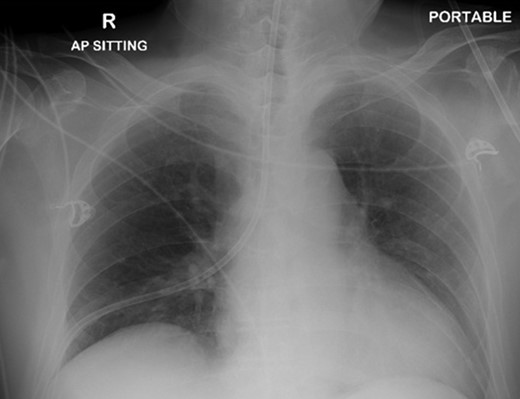

A 72-year-old male was admitted to a tertiary hospital following a cerebrovascular accident. His neurological deficits were global aphasia, dysphagia and right hemiplegia. He underwent a routine NGT change with a small bore NGT by an experienced nurse on Day 2 of admission. The nurse was unable to obtain any aspiration from the newly inserted NGT and a chest radiograph was done to confirm placement as per hospital protocol. This showed a malpositioned NGT, traversing the right main bronchus with the tip of tube in the right costophrenic sulcus (Fig. 1). She was alerted about the chest radiograph findings and removed the tube before reinserting another NGT. The subsequent aspiration from the NGT had a pH of 7, hence another chest radiograph was done which now demonstrated a right pneumothorax (Fig. 2). The pneumothorax was likely due to intrapulmonary placement of the earlier NGT.

Chest x-ray showing the nasogastric tube, traversing the right main bronchus with the tip in the right costophrenic sulcus.